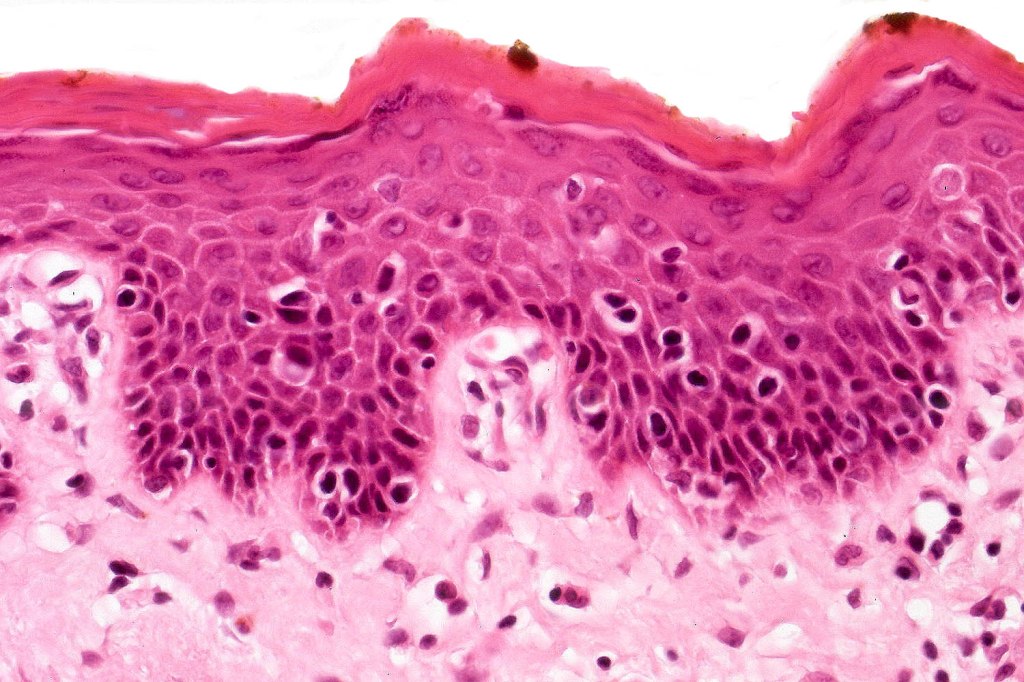

Histological features

The histological hallmark of mycosis fungoides is the presence of large atypical lymphocytes with a convoluted/cerebriform nuclear border (Sézary cells). These may be found at the epidermal-dermal jnuction and as collections within the epidermis (Pautrier microabscess). These are most easily found in plaque stage disease. The epidermal component can be subtle in patch stage disease and is often lost in tumor stage dsease. The classification into patch, plaque & tumor stage disease is less helpful histologically as the features merge from one to the other. It is all a matter of degree.

Tumor Stage Disease

•Epidermotropism is often minimal or absent

•Dense, broad diffuse or nodular, dermal infiltrate often extending into the subcutaneous fat

•Abundant Sézary cells. Frequently accompanied by very pleomorphic forms

•Mitoses often abundant, frequently abnormal

•CD30 expression correlates with transformation (cells X4 size of small lymphocytes comprising 25% or more of the infiltrate or the presence of a distinct large nodule)